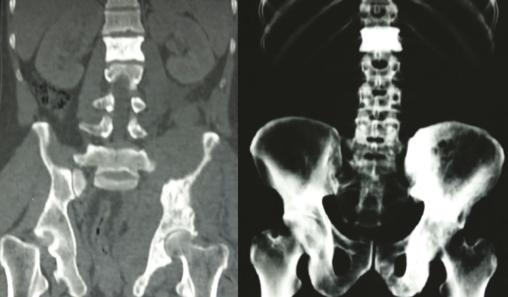

Les radiographies standards mettent en évidence une vertèbre ivoire L1 ainsi qu’une ostéocondensation de l’os iliaque gauche (fig. 1 ). Le scanner thoraco-abdomino-pelvien montre une atteinte osseuse mixte de l’aile iliaque gauche (fig. 2 ), un envahissement des parties molles (avec augmentation des volumes des muscles fessiers et du psoas [fig. 3 ] expliquant la sciatalgie), une néphromégalie unilatérale, une splénomégalie nodulaire et de multiples adénopathies abdomino-pelviennes et thoraciques.

Les radiographies standards mettent en évidence une vertèbre ivoire L1 ainsi qu’une ostéocondensation de l’os iliaque gauche (

Sur les clichés conventionnels, on décrit trois types de lésion : lytique (la plus fréquente avec 50 à 80 % des cas)2, condensante et mixte. L’ostéocondensation isolée est rare (5 % des cas).9 Elle peut réaliser l’aspect classique de la vertèbre ivoire qui est plus fréquemment rencontré dans le lymphome de Hodgkin que dans les lymphomes non hodgkiniens.2 L’association d’une lésion osseuse et d’une importante infiltration des tissus mous en regard alors que la corticale est conservée ou finement mitée est évocatrice du lymphome.9 Dans les cas où l’infiltration lymphomateuse est confinée à la cavité médullaire, les radiographies standards peuvent être normales. La tomographie par émission de positons est l’examen de référence pour evaluer les atteintes osseuses et extra-osseuses.

La tomodensitométrie (TDM), quant à elle, permet de déterminer le stade et l’extension du lymphome et d’assurer le suivi des patients. L’imagerie par résonance magnétique (IRM) est un examen très sensible pour l’étude de l’envahissement des parties molles et celle de l’extension dans la moelle osseuse. L’infiltration lymphomateuse apparaît en hyposignal ou sous forme de signal hétérogène en T1 et en hypersignal T2 avec prise de contraste après injection de gadolinium.